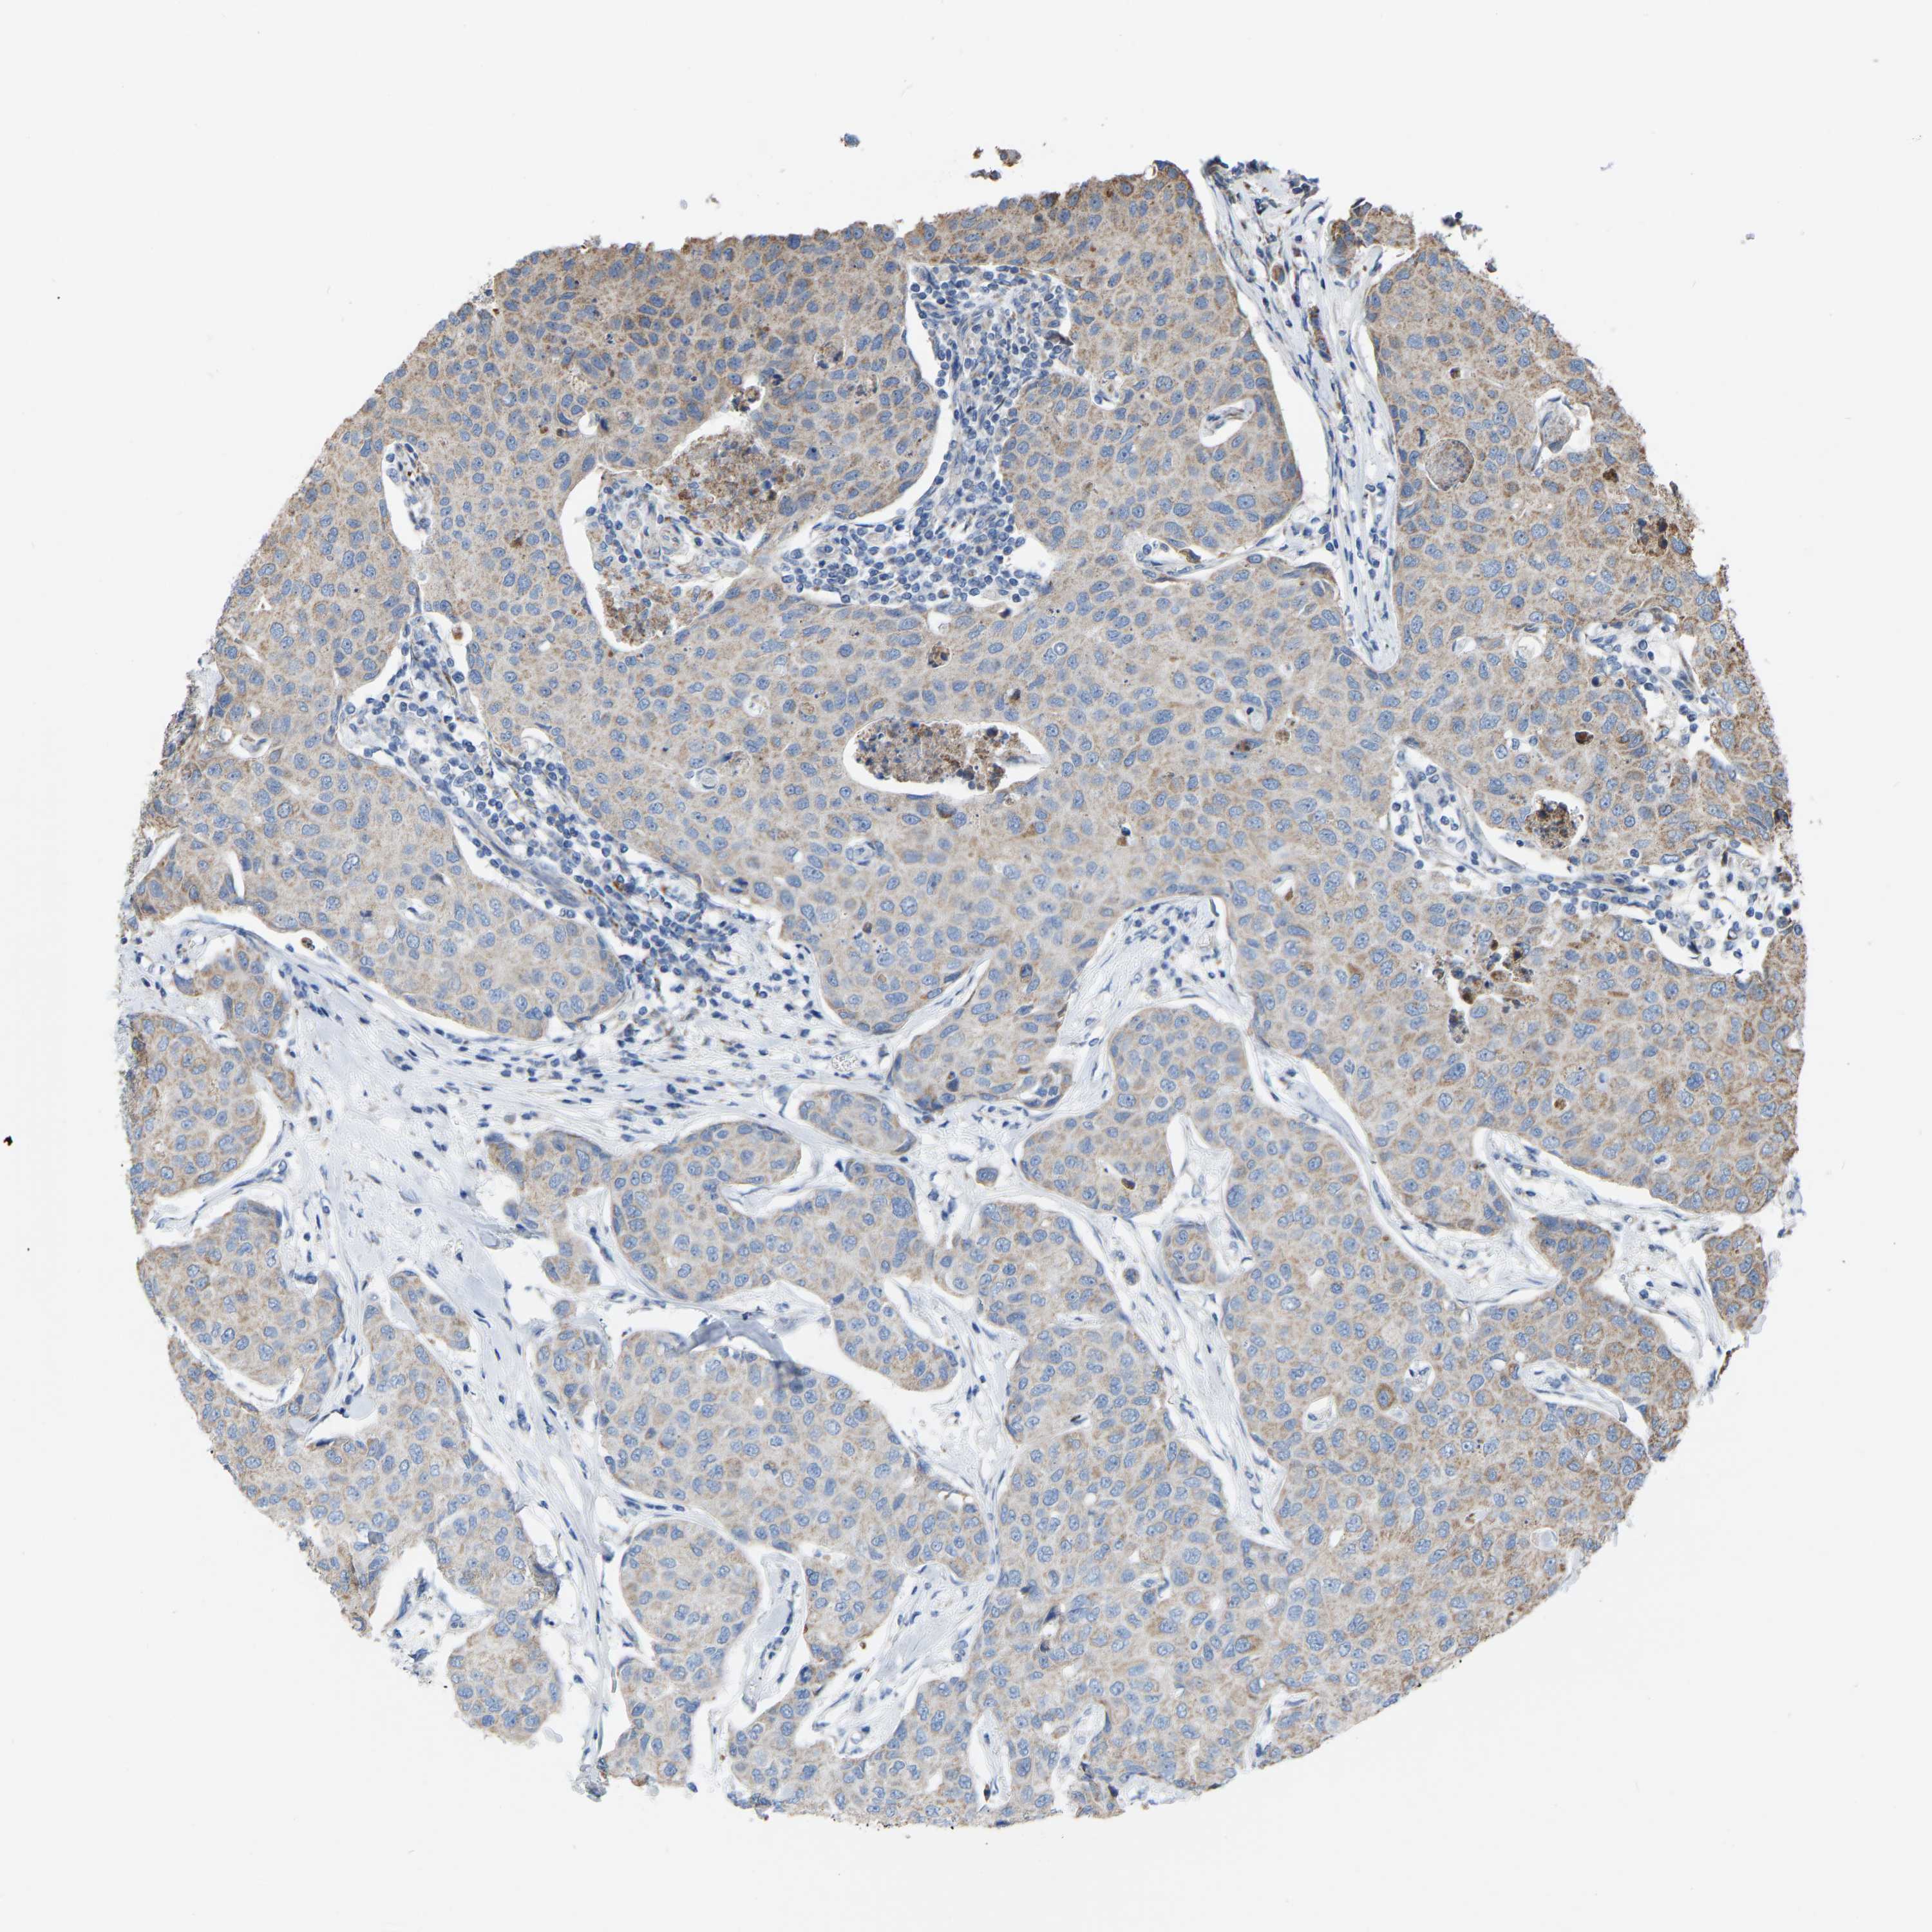

CANCER BREAST CANCER Show tissue menu

BRCA TCGA BRCA VALIDATION PROTEIN EXPRESSION